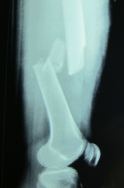

Hasil ronsen  pada patah tulang remuk dan bergeser

Penanganan medis lanjut patah tulang bertujuan untuk mengkondisikan penyembuhan/ penyambungan tulang seoptimal mungkin dan mengurangi komplikasi akibat patah tulang yang mungkin terjadi.  Beberapa pemeriksaan penunjang sederhana seperti foto ronsen dan laboratorium darah seringkali dilakukan untuk menegakkan diagnosa patah tulang dan mengetahui kondisi penderita, dan hanya pada kasus-kasus tertentu diperlukan pemeriksaan penunjang khusus lain seperti USG, arteriografi, dan CT Scan.  Penanganan patah tulang tidak selalu harus dengan operasi.  Pada kasus patah tulang sederhana, dapat dilakukan pemasangan gips, bidai khusus, mitella, ransel perban, maupun pembersihan dan penjahitan luka di IGD sesuai kebutuhan berdasarkan tingkat keparahan patah tulang.  Pada kasus berat, seperti misalnya:  kondisi luka kotor atau luka luas, patah tulang remuk, patah tulang yang cenderung akan bergeser, patah tulang di dalam sendi, dan patah tulang disertai cedera pembuluh darah atau saraf, barulah dipertimbangkan untuk tindakan operasi. Tindakan operasi seperti pemasangan pen maupun fiksasi eksterna dilakukan bila diperkirakan manfaat yang diperoleh lebih besar daripada resikonya.  Selain itu pemberian obat-obatan seperti antitetanus, antibiotik, dan obat pereda nyeri juga diberikan tergantung indikasi pada masing-masing kasus.